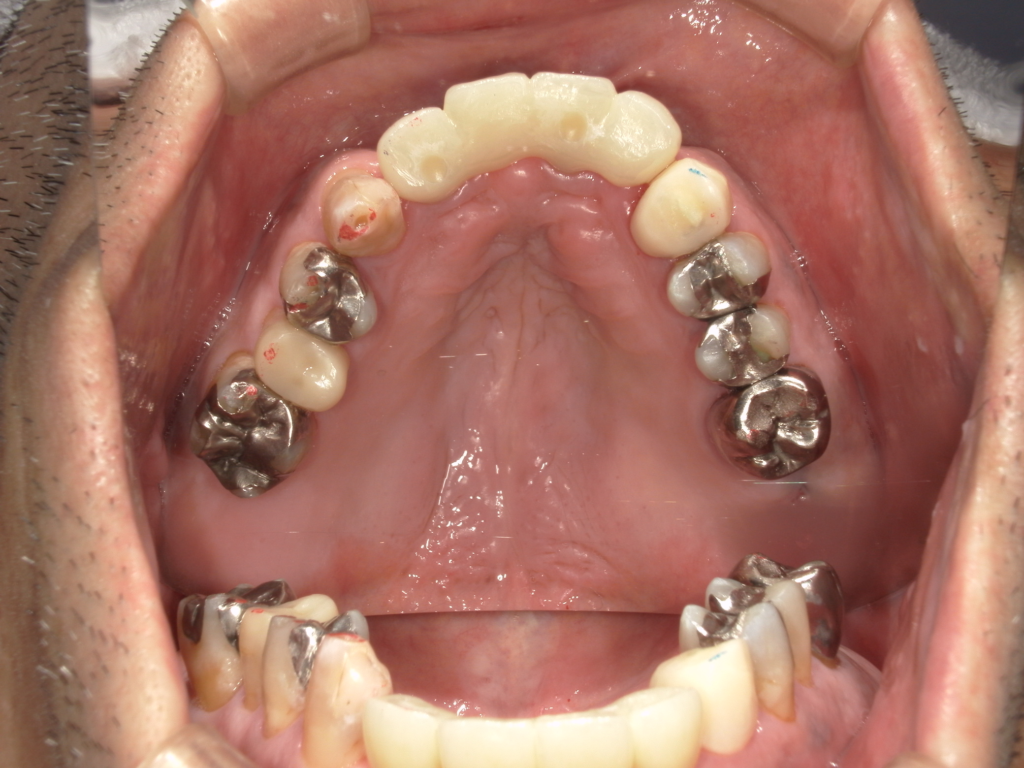

Y様インプラント実例 #44

左の上下の奥歯をインプラントで治療しています。

左下の奥歯は歯を抜くのと同時にインプラントの埋め込みを行っています。

被せものは上下、セラミックスで作っています。

治療前

治療後